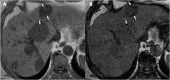

Hydatid disease is a worldwide zoonosis endemic in many countries. Liver echinococcosis accounts for 60-75% of cases and may be responsible for a wide spectrum of complications in about one third of patients. Some of these complications are potentially life-threatening and require prompt diagnosis and urgent intervention. In this article, we present our experience with common and uncommon complications of hepatic hydatid cysts which include rupture, bacterial superinfection, and mass effect-related complications. Specifically, the aim of this review is to provide key imaging features and diagnostic clues to guide the imaging diagnosis using a multimodality imaging approach, including ultrasound (US), computed tomography (CT), magnetic resonance (MR), and endoscopic retrograde cholangiopancreatography (ERCP).